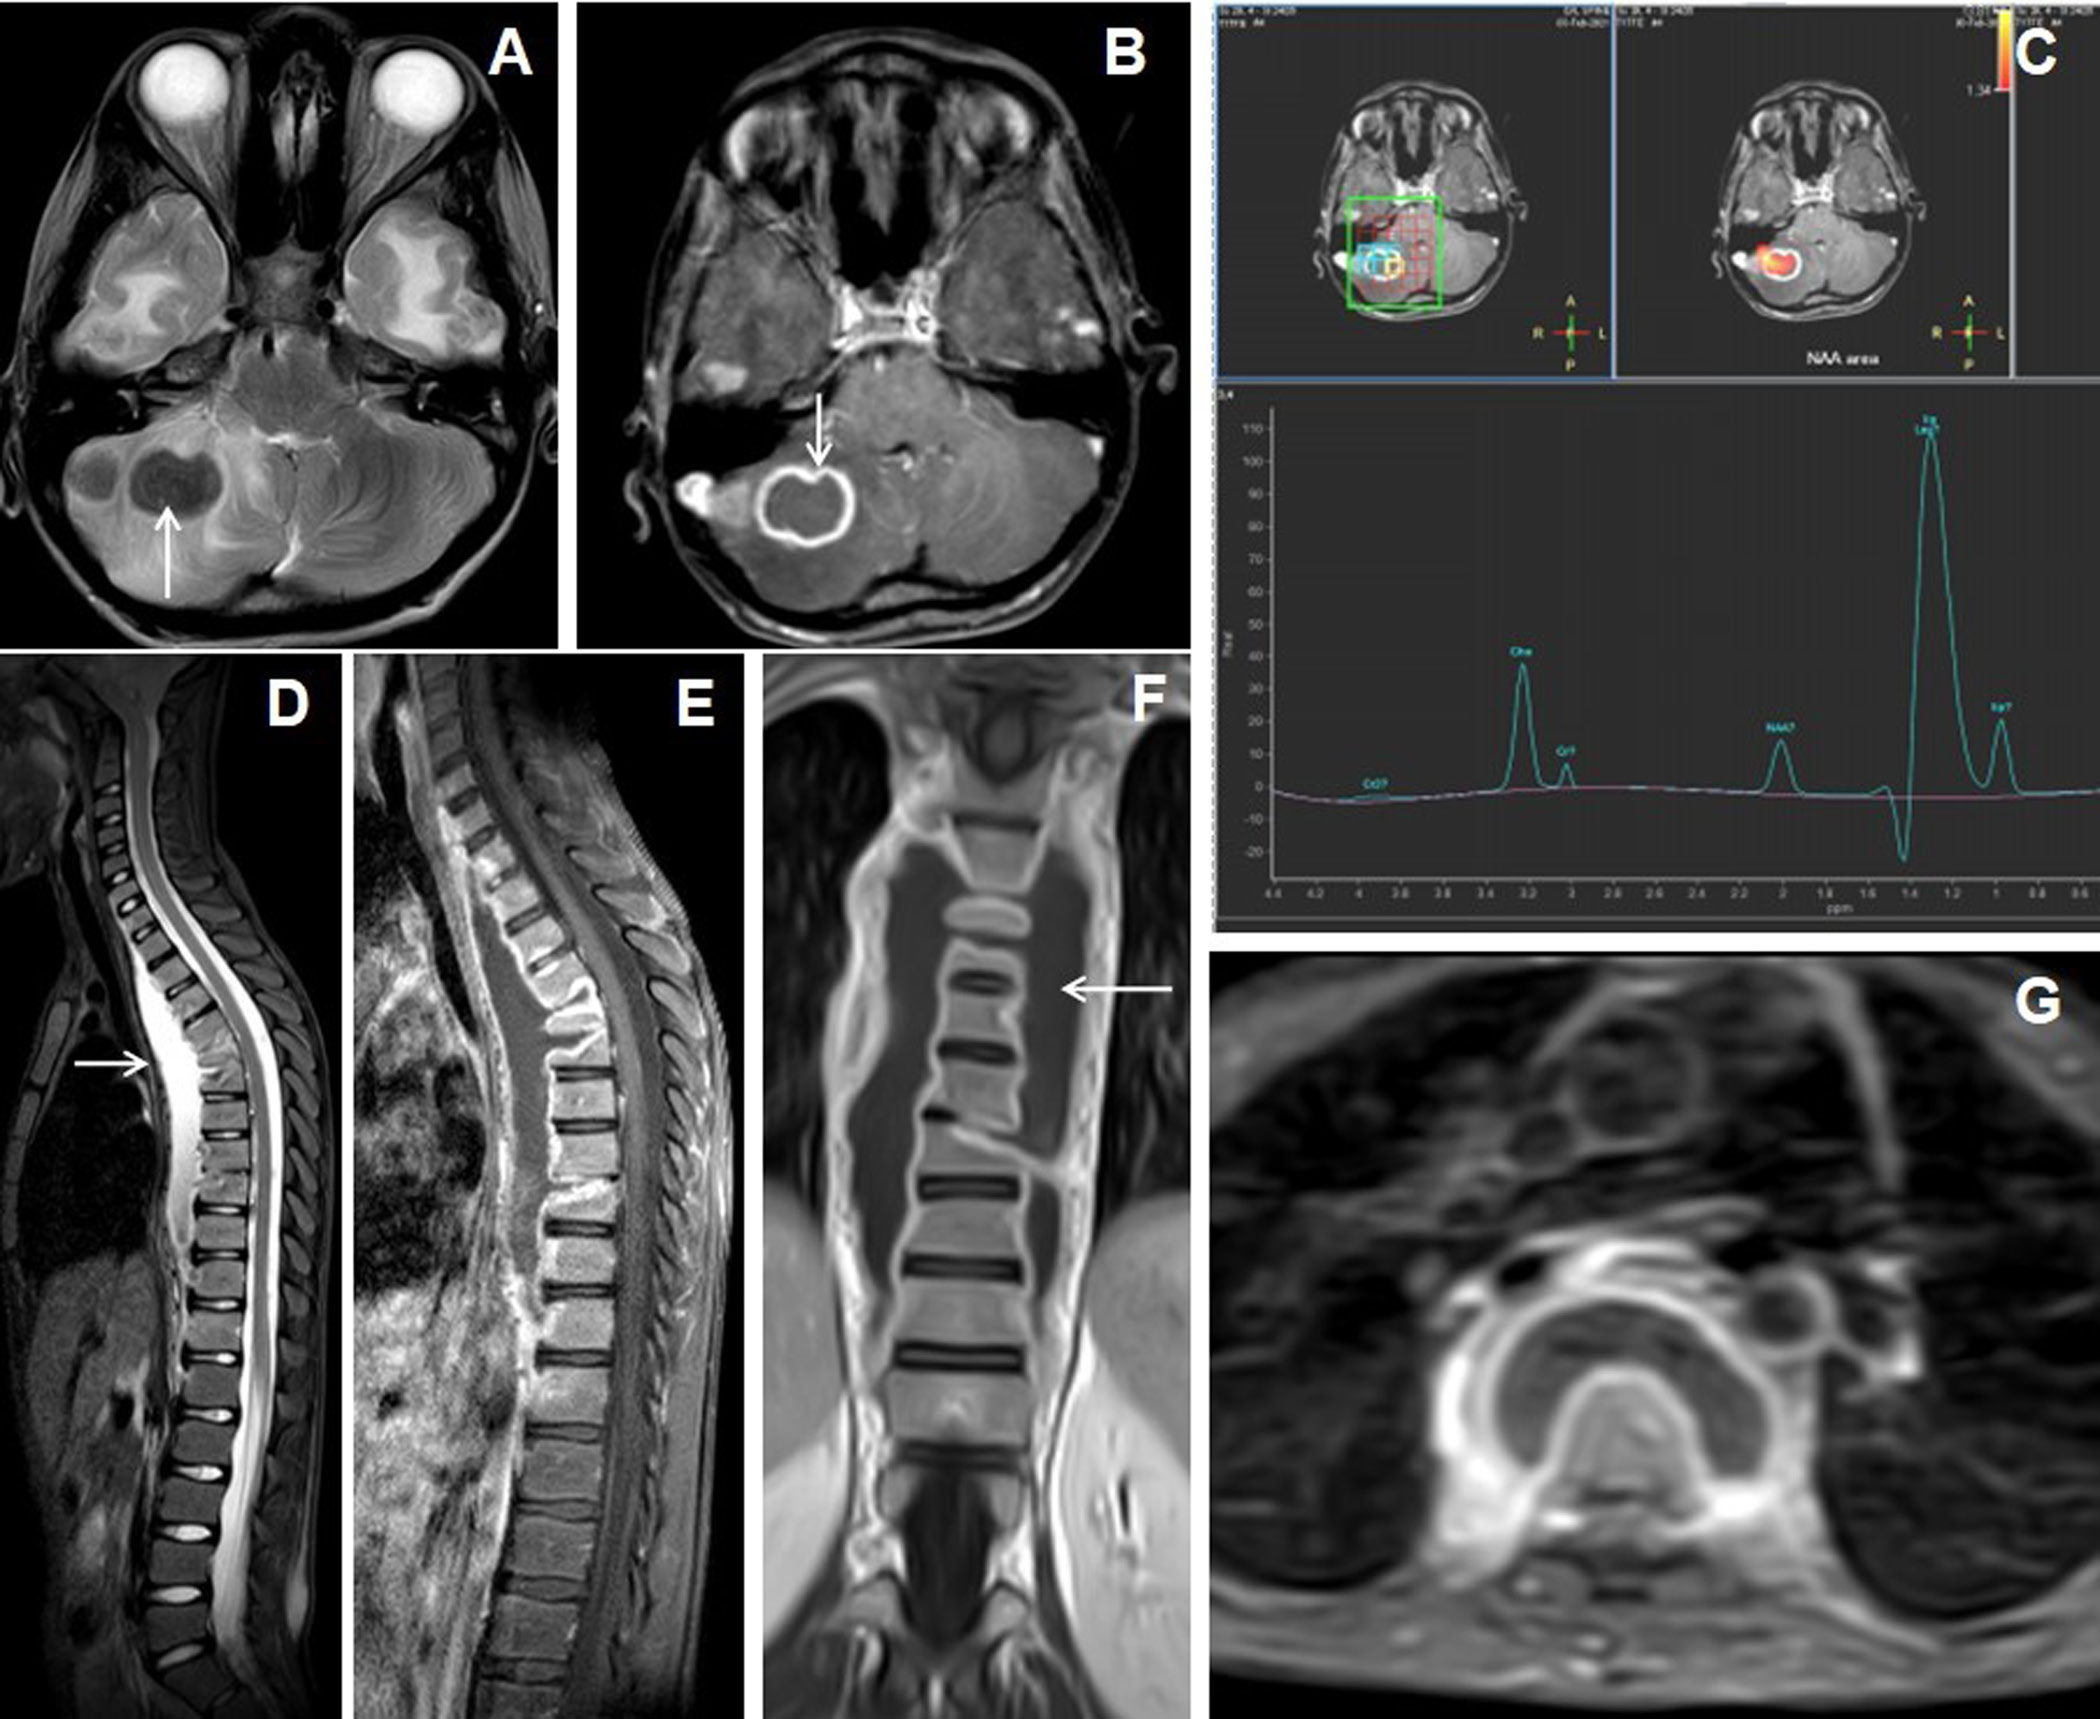

Figure 5. 13 years male presentedwith headache, vomiting and chronic backache. Cranial MRI with axial T2W image of the brain (A) shows hypointense nodular lesions in right cerebellum with perifocal edema. Axial post-contrast image (B) shows a larger irregular shaggy peripherally enhancing rim-like lesion with central necrosis (arrow) and adjacent laterally located solid nodular enhancing satellite lesion. MR spectroscopy (TE 144) image (C) shows lipid peak in 1.3ppm with slightly raised choline peak. The sagittal STIR image of spine (D) shows abnormal STIR hyperintensities in multiple lower cervical and dorsal vertebrae with partial collapse of the D5, D6 and D9 vertebrae and associated T2 hyperintense long segmental prevertebral collection in the cervico-dorsal region (arrow).